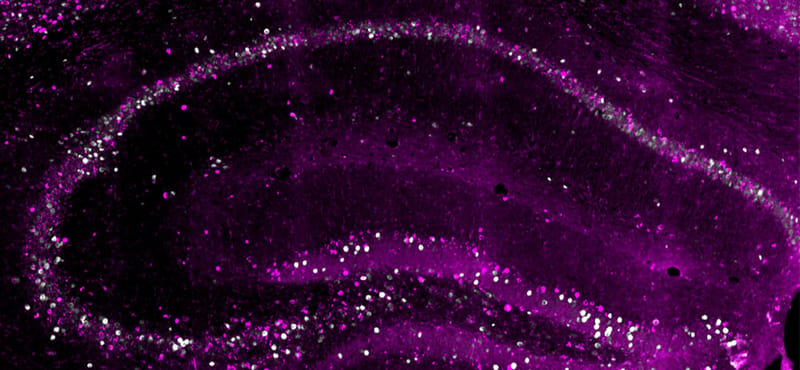

Egy emlékről három másolat létezik az agyban, mindegyikhez máshogy lehet hozzáférni

Nem bízza a véletlenre az agyunk az információk tárolását, egy emlékről másolatokat is készít. Az emlékek azonban nem maradnak változatlanok a rögzítésük után, a tartalmuk frissíthető esetleges külső vagy belső hatások esetén – derítették ki svájci kutatók.